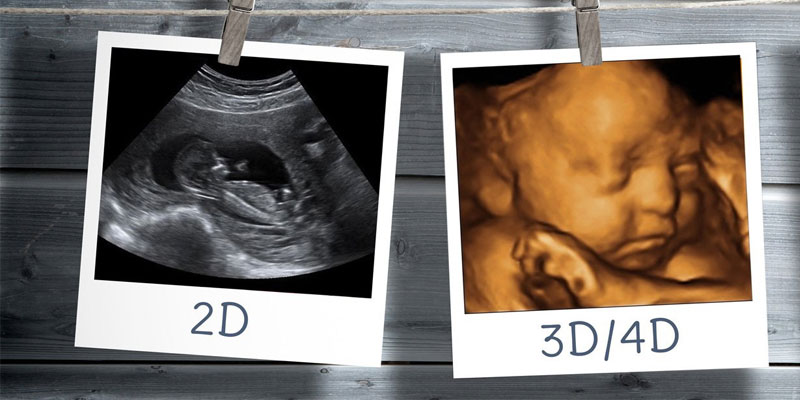

Ultrasound (3D/4D)

Swastik Imaging provides expert and adaptable ultrasound services in Gurgaon with real-time and thorough diagnostic data. Using colour ultrasonography, a foetus inside the mother can be seen in 3D or 4D. Parents receive a beautiful view of their unborn child, and doctors may be able to see information that assist them more accurately assess the foetus' health.

The technology combines advanced skin rendering techniques to generate colours that are realistic with a virtual light source that can be adjusted. Every feature, including the fetus's blood flow and every bump and fold, is highlighted as the virtual light source creates clarity and shadows. Our large staff of skilled nurses and medical professionals is dedicated to giving your infant the finest care possible.